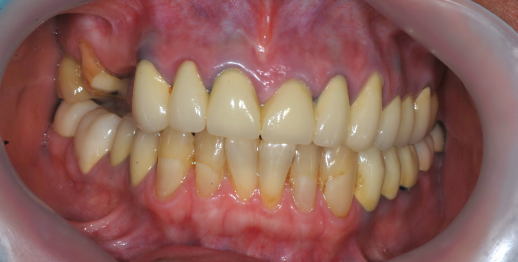

Upper jaw dental implants and bone graft

55 y.o, Russia

Operating dentist: Roh Hyun Ki